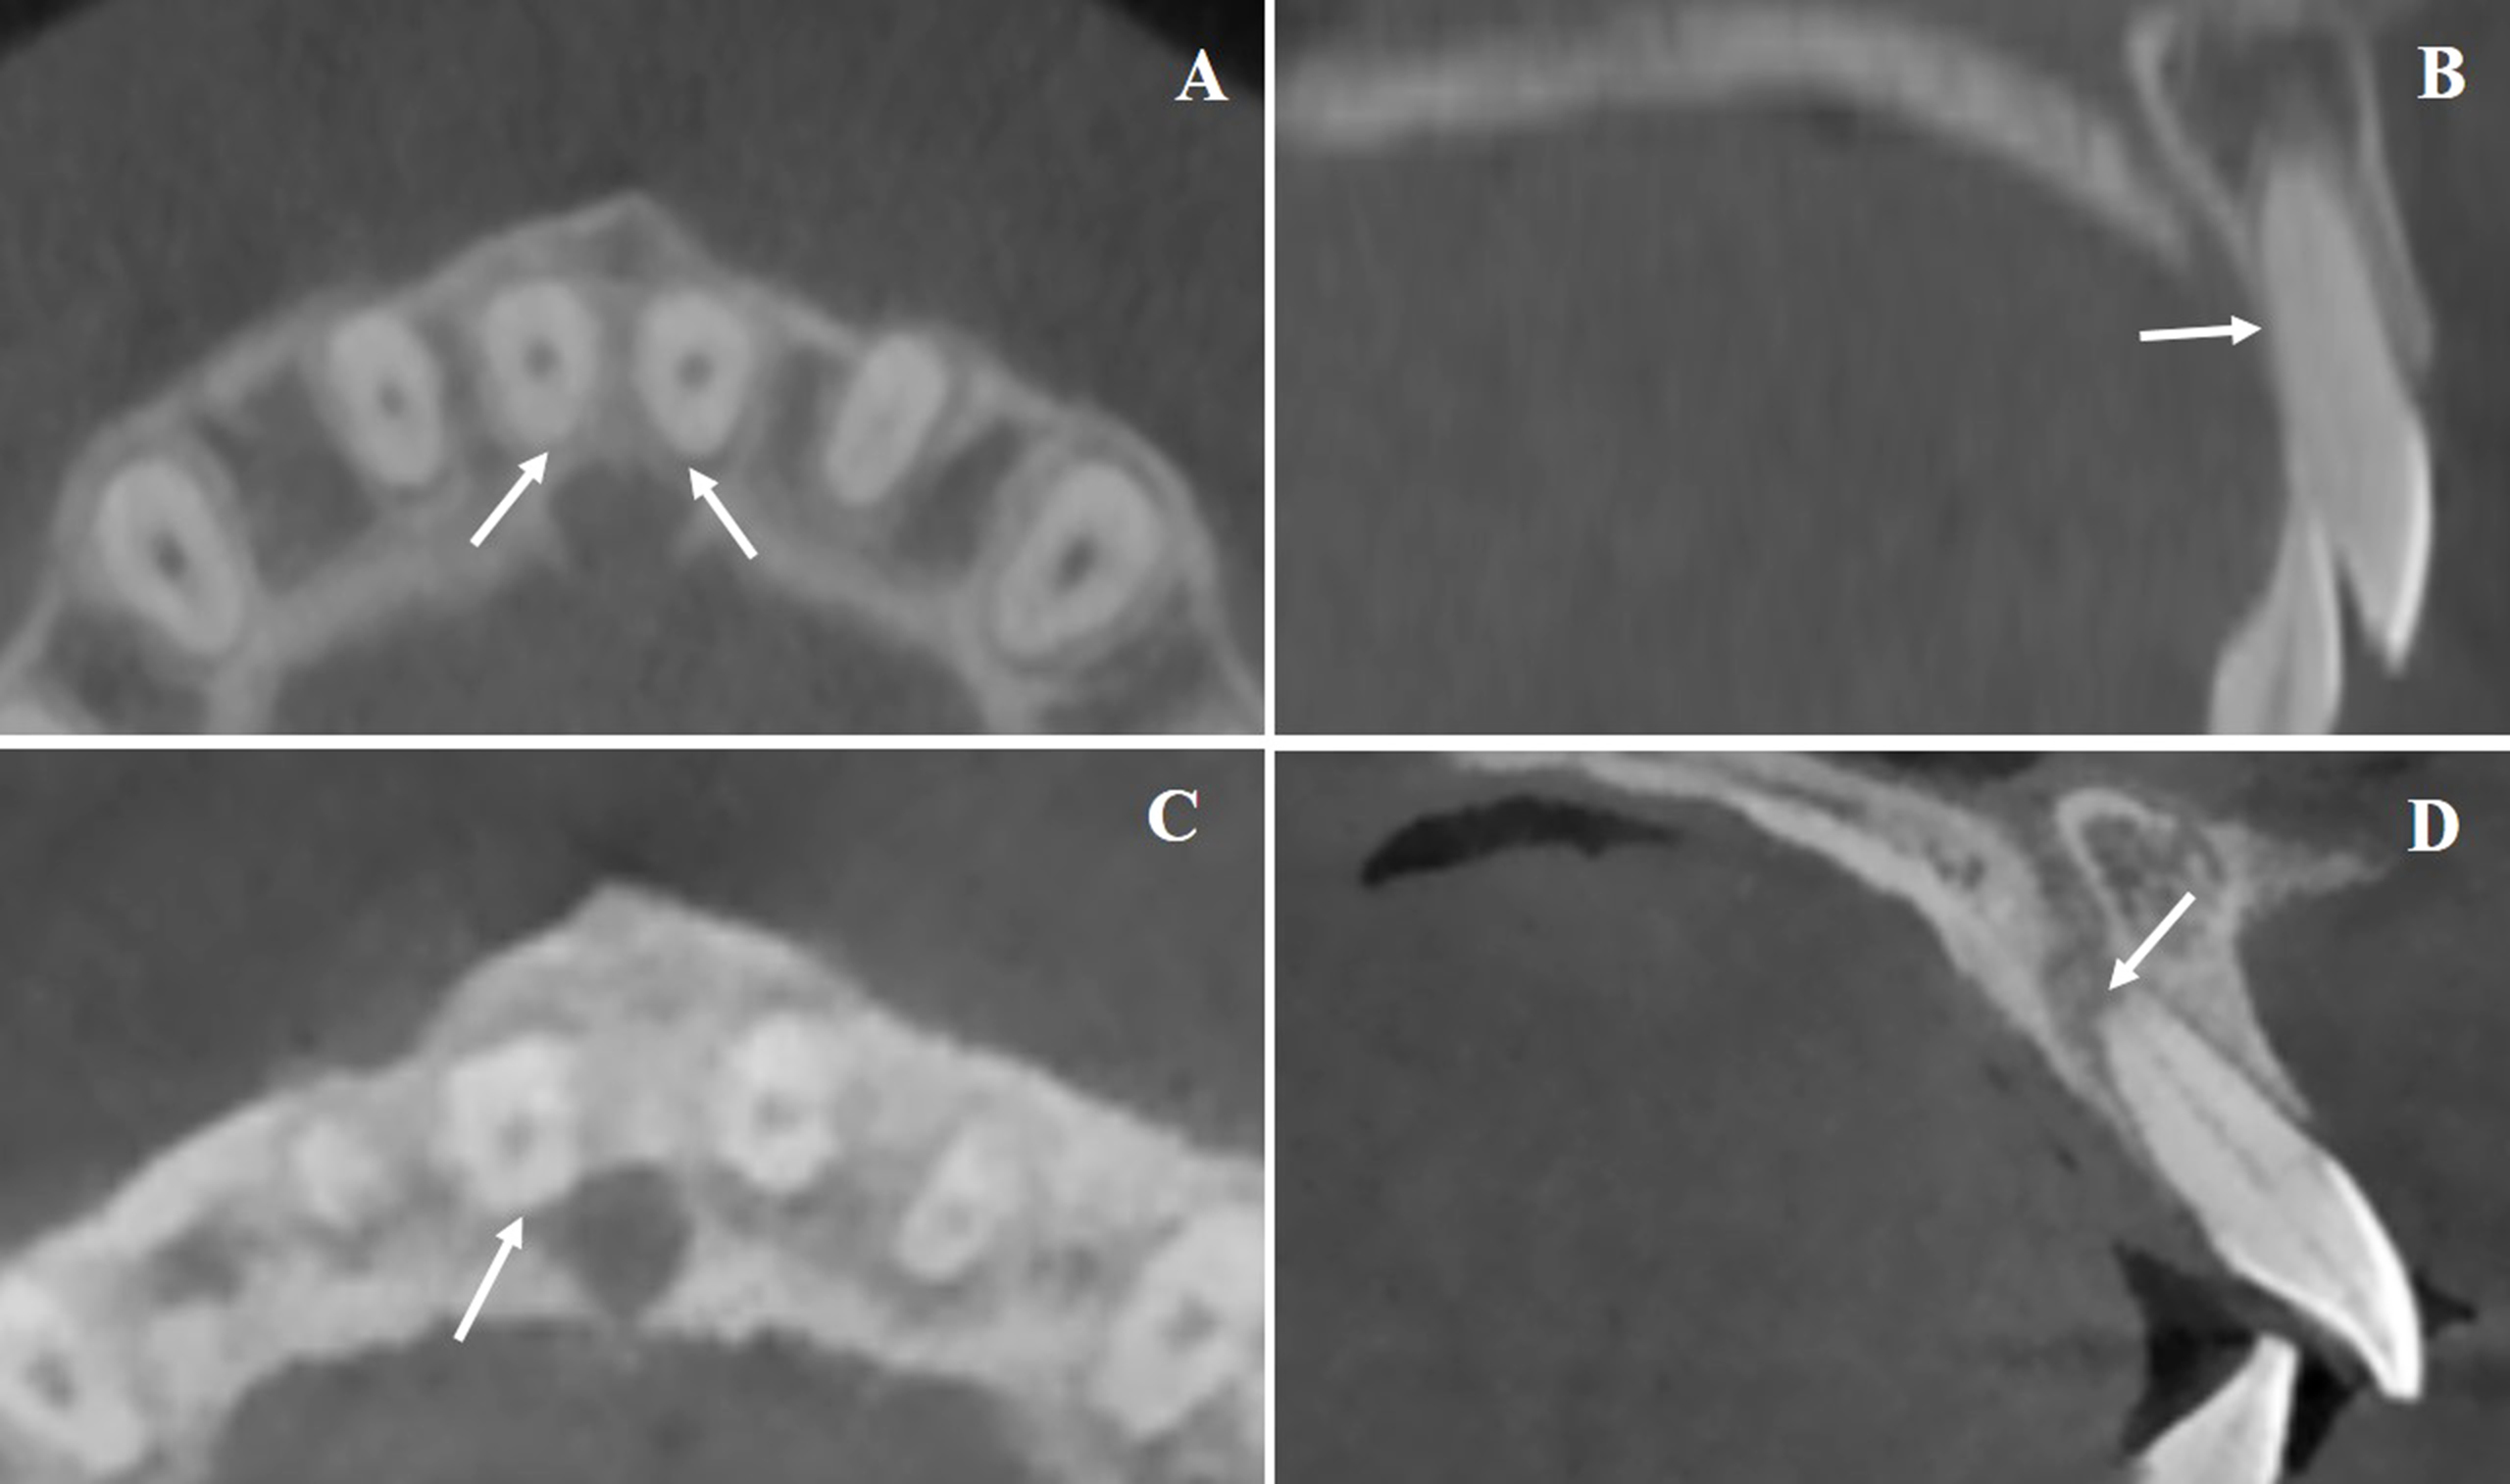

Based on CBCT evaluation, post-treatment root-to-IC relationships were categorized as follows: separation, increased distance between root and IC cortical boundary; approximation, root nearing the IC without contact; contact, root abutting the IC cortical margin (distance = 0, Fig. 2A-B); and invasion, root partially or fully penetrating the IC cortical plate or lumen (distance < 0), with remaining CBW noted as zero if the lumen was involved (Fig. 2C-D).

Representative Patterns of U1 Root and Incisive Canal Proximity. A and B. Representative CBCT images showing direct contact between the incisor root and the lateral wall of the incisive canal (highlighted by arrows). C and D. Examples illustrating root invasion into the IC lumen, with cortical disruption clearly visible (indicated by arrows).